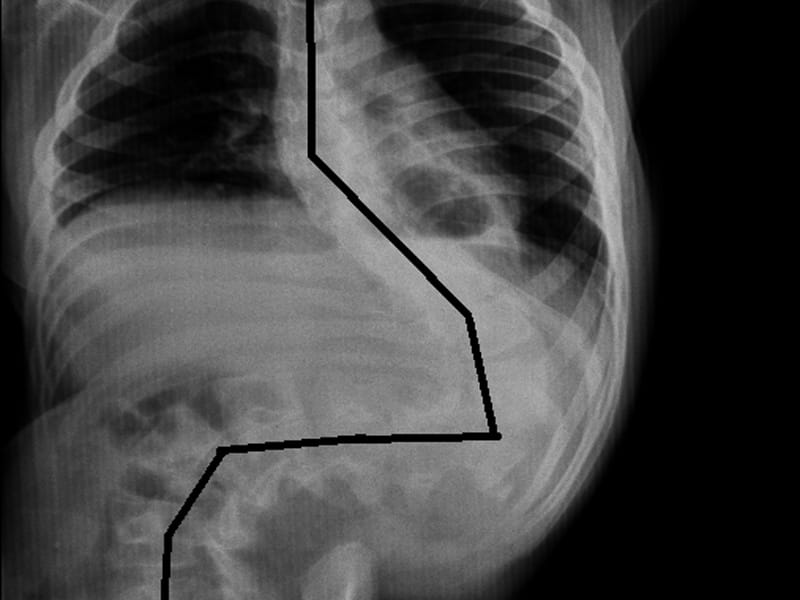

Dušanu Milanoviću (16) obolelom od cerebralne paralize hitno je potrebna operacija kičme zbog teške skolioze koja mu je ugrozila život, a ceo Svrljig uključio se u akciju prikupljanja neophodnih 805.000 dinara za Dušanovu operaciju.

Dušanu je bolest ustanovljena u trećoj godini, a pre dve godine kičma je počela da se krivi i da mu pritiska pluća, što mu je ugrozilo život. Operacija, koja podrazumeva fiksaciju kičme, besplatna je i izvodi se na beogradskoj Vojno-medicinskoj akademiji, gde, nažalost, nemaju neophodni materijal za operaciju koji košta 805.000 dinara.